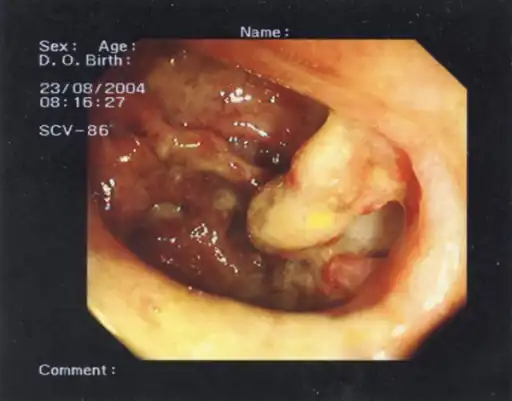

Colonoscopy is contraindicated, as it may rupture the dilated colon resulting in peritonitis and septic shock.

The pathological process involves inflammation and damage to the colonic wall with unknown toxins breaking down the protective mucosal barrier and exposing the muscularis propria.[4] There is relative destruction of the ganglion cells and swelling of the nerve fibers in the myenteric plexus, with concomitant damage to the colonic musculature.[4] This results in almost complete paralysis of the diseased segment of the colon with loss of smooth muscle substance, tone and motility.[4] This can lead to further complications as pressure builds up in the colon due to relative fecal stasis including sepsis, intestinal hemorrhage or free perforation and spontaneous decompression.[4]